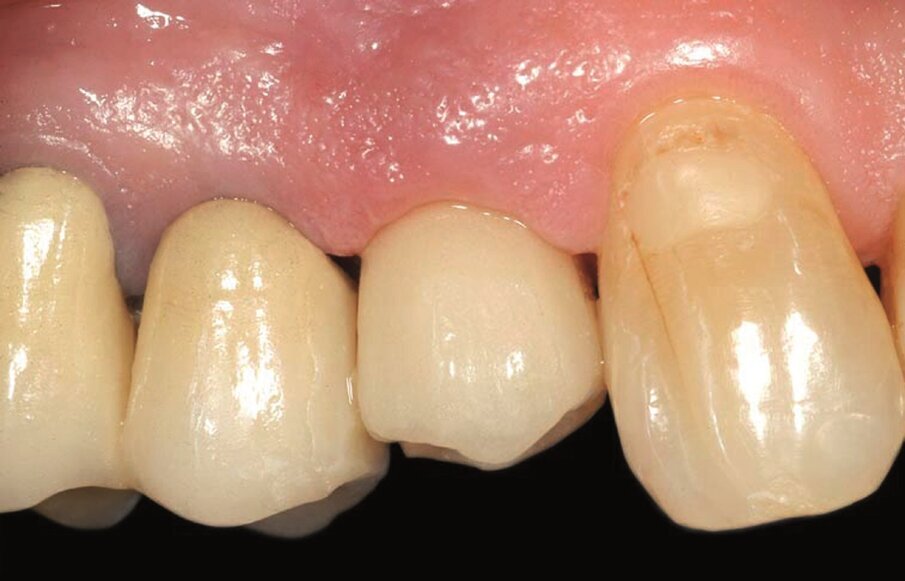

Fig. 2b_Fase protesica provvisoria. Corona provvisoria avvitata.

Fig. 2c_Fase protesica provvisoria libera da contatti occlusali.